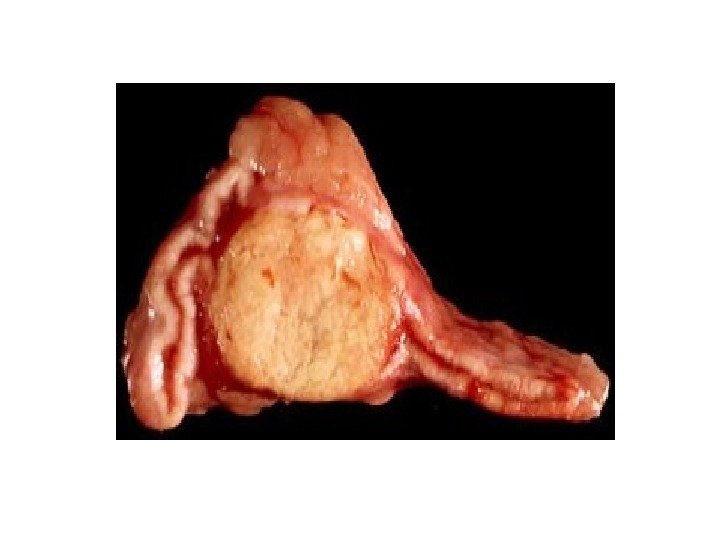

ФЕОХРОМОЦИТОМА

ФЕОХРОМОЦИТОМА